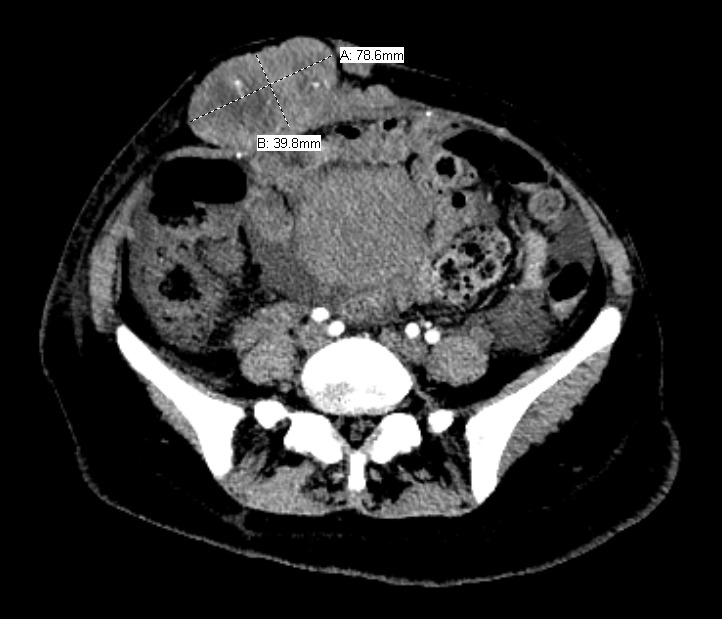

The patient delivered by spontaneous vaginal delivery at 37 weeks gestation. Her tachycardia persisted postpartum with heart rates exceeding 140 beats per minute, still of unexplained etiology. She developed a leukocytosis within the normal postpartum range but remained afebrile and without fundal tenderness. Due to increasing suspicion for malignancy, a computed tomography (CT) scan of the abdomen and pelvis was obtained, which showed a 19.0 x 17.7 x 22.5 cm heterogeneously enhancing soft tissue retroperitoneal mass with internal calcifications (Figures 1 and 2) and heterogeneously enhancing masses of various sizes in the liver and abdominal wall concerning for metastatic GIST (Figure 3). On postpartum day six, CT angiography of the chest was performed due to persistent tachycardia in the setting of a new diagnosis of a malignancy, which showed a right anterior lower lobe segmental and subsegmental pulmonary embolus. The patient was started on therapeutic low-molecular-weight heparin and trans-thoracic echocardiography was performed, which was unremarkable.

Our patient presented with several unique challenges that delayed the diagnosis of a cancer recurrence. First, she presented late to prenatal care at 34 weeks gestation and delivered less than three weeks later. The superficially palpable abdominal mass appreciated at her initial visit was seemingly confirmed on abdominal ultrasound to be a benign leiomyoma, but was later revealed to be an extra-uterine soft tissue metastasis (Figure 3). GIST during pregnancy is often discovered due to size-greater-than-dates, but in the case of our patient it was difficult to arrive at an accurate estimation of either, because the patient did not know the date of her last menstrual period, and because it was believed that she had an enlarged, fibroid uterus. Additionally, because the patient’s initial surgery was done internationally, the operative report and her medical records were not attainable for review, making it difficult to assess her risk for recurrence. She did, however, present with diminished appetite and weight loss in the third trimester, which is never normal and has been associated with fetal growth restriction and poor perinatal outcomes (Mola, Kombuk, and Amoa 2011). Her cachexia and early satiety were later explained by mass effect from the tumor compressing her stomach. Following neoadjuvant imatinib therapy, the patient’s tumor initially decreased in size with significant improvement in her appetite and nutritional status; however, this response was complicated by tumor necrosis with significant intra-abdominal bleeding, as well as by multiple bowel perforations, which ultimately led to her death.